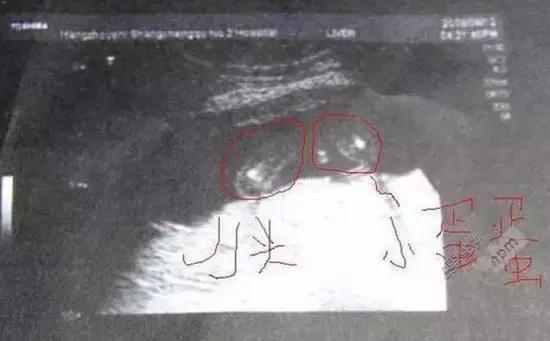

二、孕囊辨别生男生女?

孕囊是怀孕最初的形态 , 是原始的胎盘组织被羊膜、血管网包裹的小胚胎 。 那时候胎儿还没有形成 , 胎芽出现时已经有胎心跳动了 。 很多的医生看男女就是通过孕囊来看的 , 那么孕囊是如何看出胎儿性别的呢 。

怀孕5周以后 , 孕囊就可以看到了 , 如果想要辨别胎儿性别最好要8周以后 。 那么孕囊如何辨别生男生女?

第一、如果您照的B超孕囊呈长条形 , 类似上图那么男宝宝的概率大 。

第二、如果您照的B超孕囊呈椭圆形 , 那么女宝宝的概率比较大 。